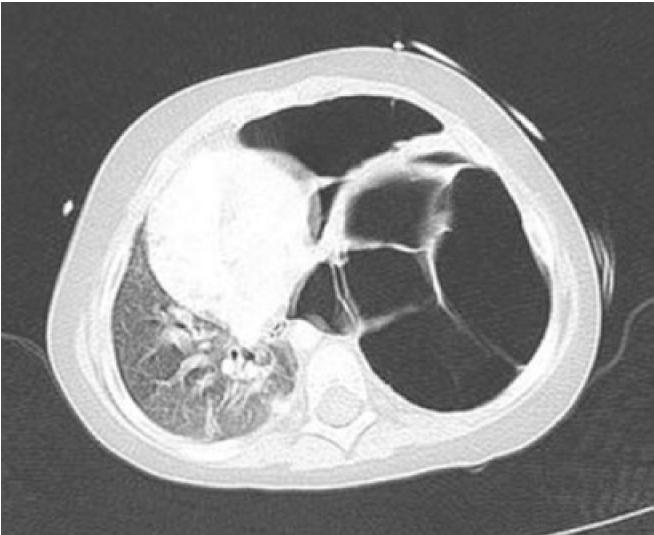

②肺部感染反复发作,并可危及生命;常并发支气管扩张、肺空洞/大泡、肺结节、支气管胸膜瘘等肺结构性病变。这种肺结构病变又易带来真菌、非结核性分枝杆菌等机会性感染。

- 肺大泡

4,控制肺部并发症:大面积、持续的肺大泡可能需要采用肺段切除、甚至肺叶切除进行治疗。但该情况很少见。或许跟预防性抗菌治疗减少肺部并发症有关。